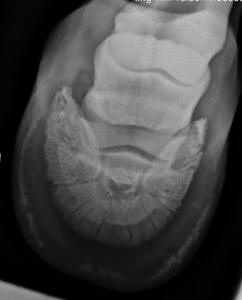

Insert Photo

4ramey3. Caption: This is a radiograph of a

horse with long-term “sub-clinical” laminitis (this means that, for years, no

one noticed except the horse). When the outer perimeter of the coffin bone loses

mass and/or becomes wavy or

fuzzy, it is common that the horse

will have a difficult time growing a healthy sole—permanently. This is why it is

so important to take action (dietary changes) when you first notice the

slightest indicators of laminitis. Photo reprinted from the book Care and

Rehabilitation of the Equine Foot, P. Ramey.